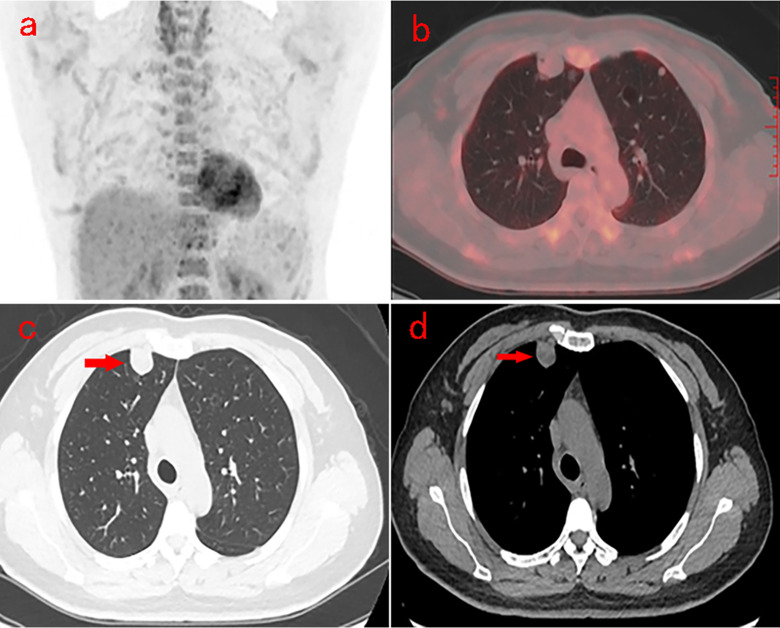

Case presentation: A 47-year-old female underwent an 18F-fluorodeoxyglucose(FDG) positron emission tomography/computed tomography(PET/CT) scan, revealig multiple solid and cystic nodules with mild FDG uptake in both lungs. The tumor exhibited an adenoid or papillary structure, covered by monolayer mucous columnar epithelium and pseudostratified ciliated columnar epithelium, with abundant mesenchymal cells. Nuclei were oval, fusiform, or polygonal, resembling ovarian-like stroma, and showed mild nuclear atypia without atypical mitoses. Immunohistochemical analysis indicated: CK (epithelial cell +), P63 (epithelial basal cells +), CK7 (epithelial cell +), CK20 (-), TTF-1 (epithelial cell +), napsin A (partial epithelial cell +), α-inhibin (-), S100 (-), SMA (-), EMA (epithelial cell +), CEA (-), WT-1 (mesenchymal cells +), ER (mesenchymal cells +), P16 (partial mesenchymal cells +), CD10 (mesenchymal cells +), and Ki-67 (2% +).